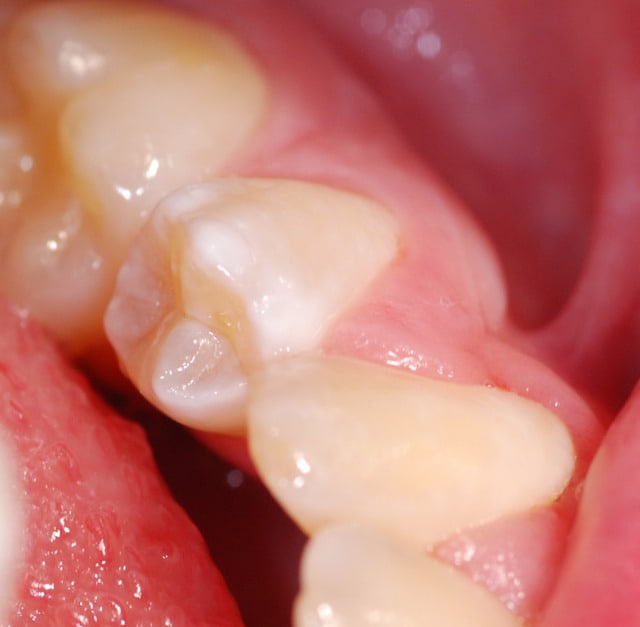

Bonjour,

Je finalise ma thèse sur la MIH (Hypominéralisation Molaire-Incisive). Je n'ai que des photos assez médiocres... Je vois que certains d'entre vous sont très doués en photo et c'est une pathologie très courante (10-15%) : si quelqu'un a quelques clichés à m'envoyer, je lui en serai très reconnaissant. Bien sûr, son nom serait cité en référence.

PS : en pièce jointe, le mieux que j'arrive à faire, pas super...

Pour les MIH :

- Opacités délimités, contours nets

- Couleur blanc-jaune à brun, "crème" en général

- Forme des taches

- Affecte au moins une première molaire permanente et dans 75% des cas une ou plusieurs incisives permanentes. Très rarement d'autres dents (pointes canines ou secondes molaires)

- Atteintes asymétriques (on peut voir une 16 très atteinte, une 36 modérément atteinte, une 26 intacte)

Pour les fluoroses :

- Opacités à contours flous

- Blanc dans les cas légers (les plus courants en France), jaune-brun à brun dans les cas modérés ou sévères.

- Forme des stries qui suivent les périkymaties mais ces stries confluent souvent en taches ou en bandeaux

- Affecte toutes les dents d'une denture

- Atteintes symétriques Gauche/Droite

Encore merci à toi pour le temps que tu as pris.

1ère photo : fluorose légère

2ème : MIH